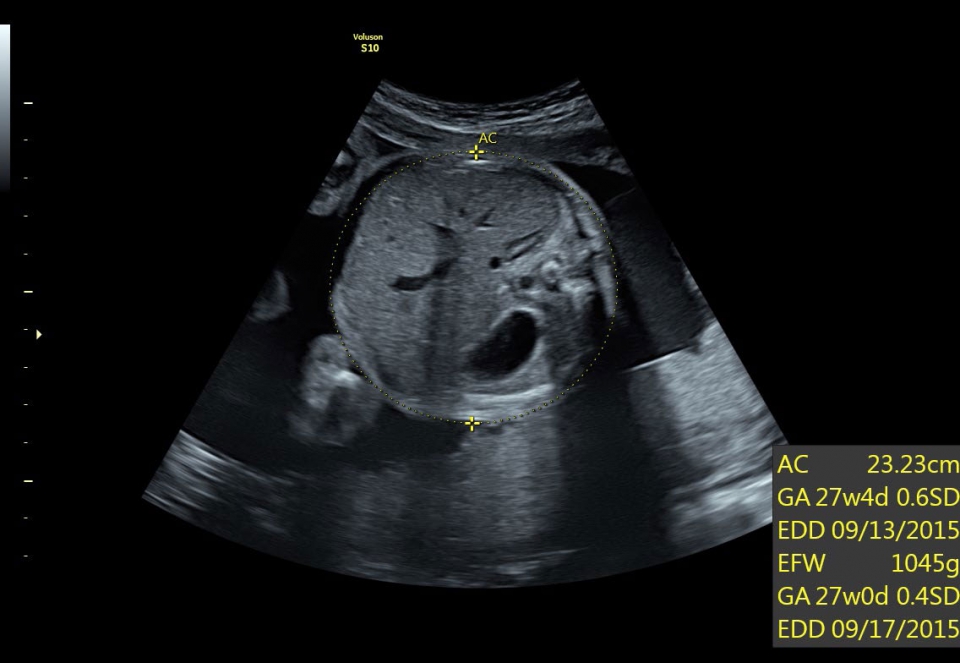

УЗИ аппарат Voluson S10 позволяет проводить обследования высочайшего уровня с максимальной точностью диагностики. Благодаря технологии Voluson Core Architecture достигнут высокий уровень качества изображений с возможностью последующей обработки и анализа даже после проведения скрининга. Технология HDlive делает изображения удивительно реалистичными и объемными.

• SonoBiometry (Полуавтоматическая биометрия): Эта технология позволяет проводить измерения биометрических параметров плода, таких как бипариетальный размер, окружность головы, окружность живота, длина бедра и длина плеча. Она упрощает процесс получения точных и надежных измерений.